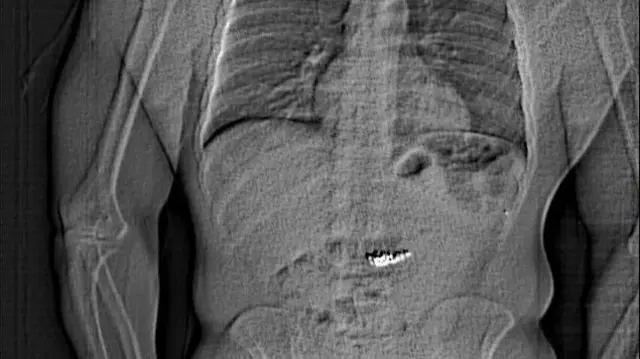

Policija je objavila rendgenski snimak za koji se čini da prikazuje ljudski abdomen sa stranim objektom unutra.